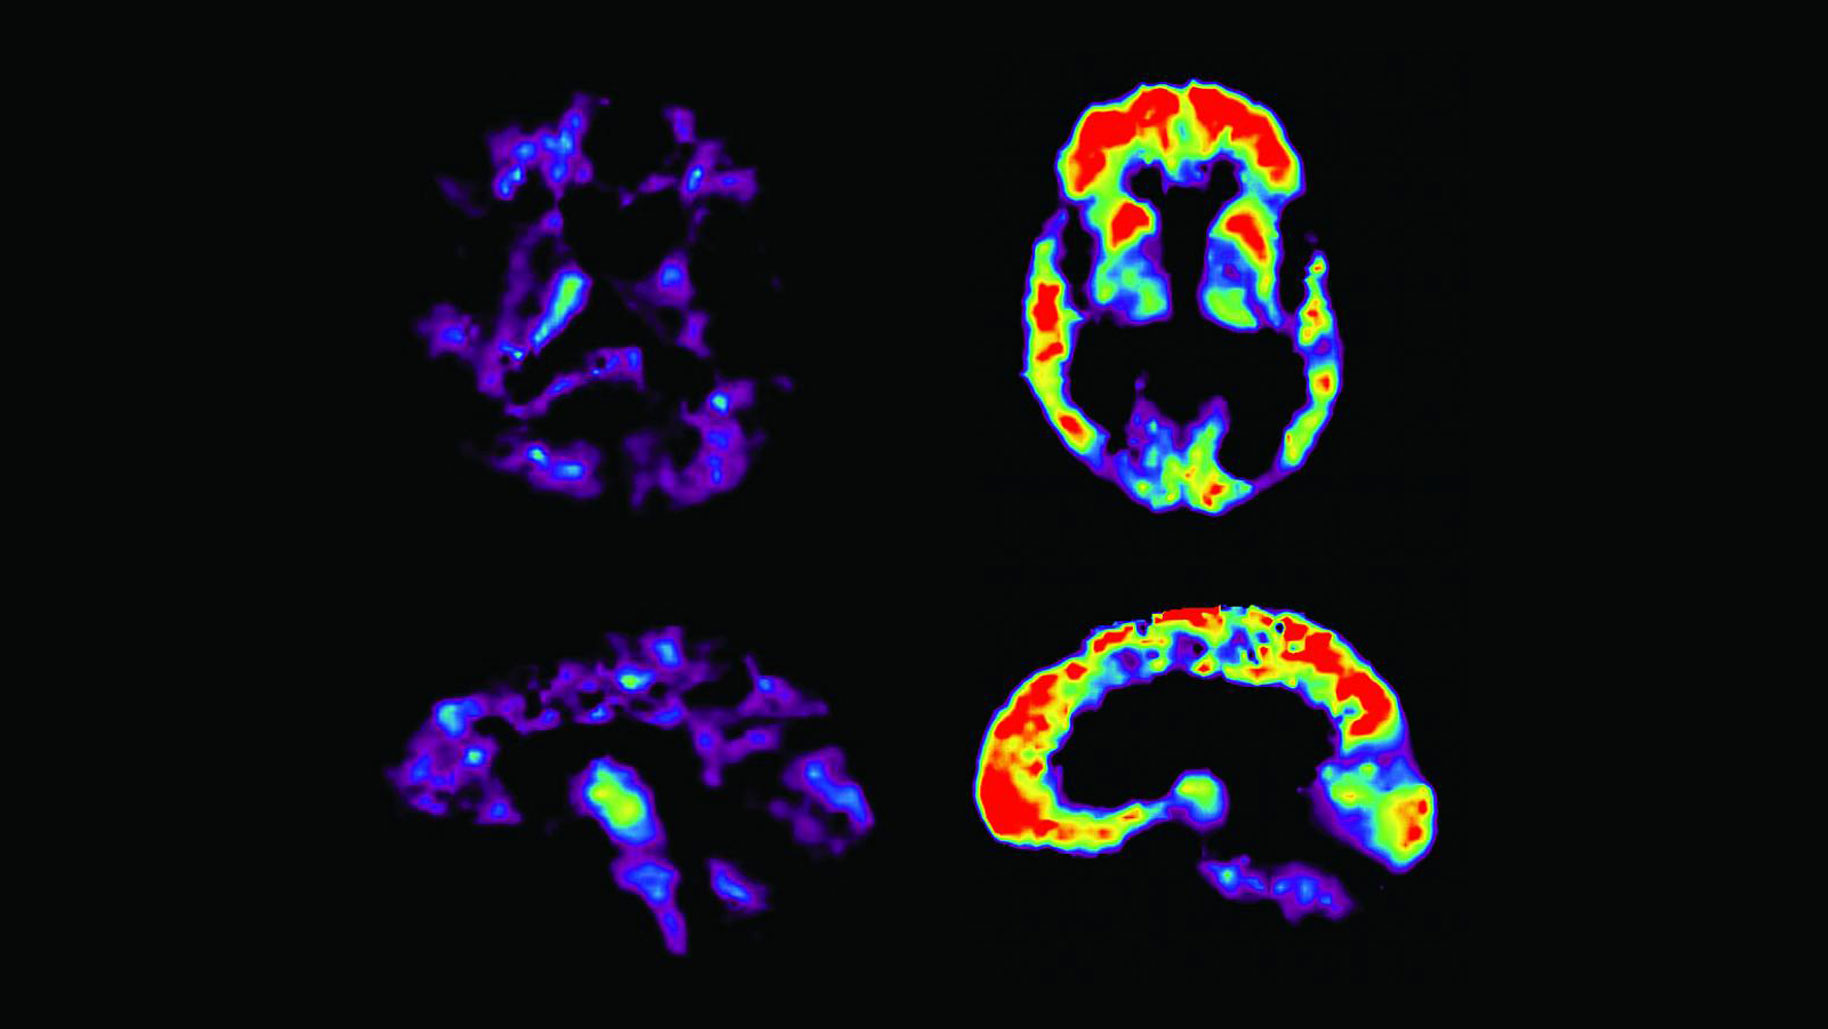

Los fármacos antialzhéimer siguen fracasando y la ciencia ya no sabe qué hacer